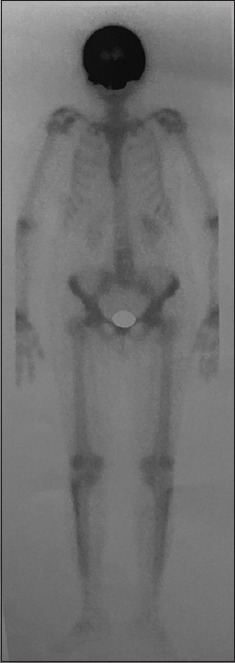

Background and aim: Paget's disease of the bone refers to a chronic cumulative disorder characterized by enhanced osteoclastic function followed by a secondary surge in osteoblastic activity. The condition can manifest as a polyostotic or monostotic bone disease with most patients having an asymptomatic presentation, although some may complain of pain localized to the affected bone while others express symptoms of nerve compression. A pagetic bone is predisposed to develop pathological fractures, bony deformities, and a rare yet detrimental transformation into osteosarcoma. Detection is often accidental when performing radiographic tests for other indications or when elevated blood levels of alkaline phosphatase (ALP) are detected. Treatment with third-generation bisphosphonates is helpful in preventing further bone resorption and, additionally, reduces bony pains that are believed to be caused by excessive metabolic activity. Here, we present a case of a middle-aged asymptomatic female with elevated serum ALP levels up to 1537 IU/L (reference range 40-150 U/L) during her pre-operative evaluation for elective cholecystectomy.99m Tc-methylene diphosphonate bone scintigraphy revealed diffuse uptake in the skull and, hence, was diagnosed as a case of isolated Paget's disease of the skull.

Relevance for patients: The rarity of this disease in Southeast-Asians, its uncontrived detection, and the isolated skull involvement, imparts high clinical relevance on this case. Early detection and management of this disease can help prevent the development of life-threatening complications in affected patients, hence decreasing the morbidity.